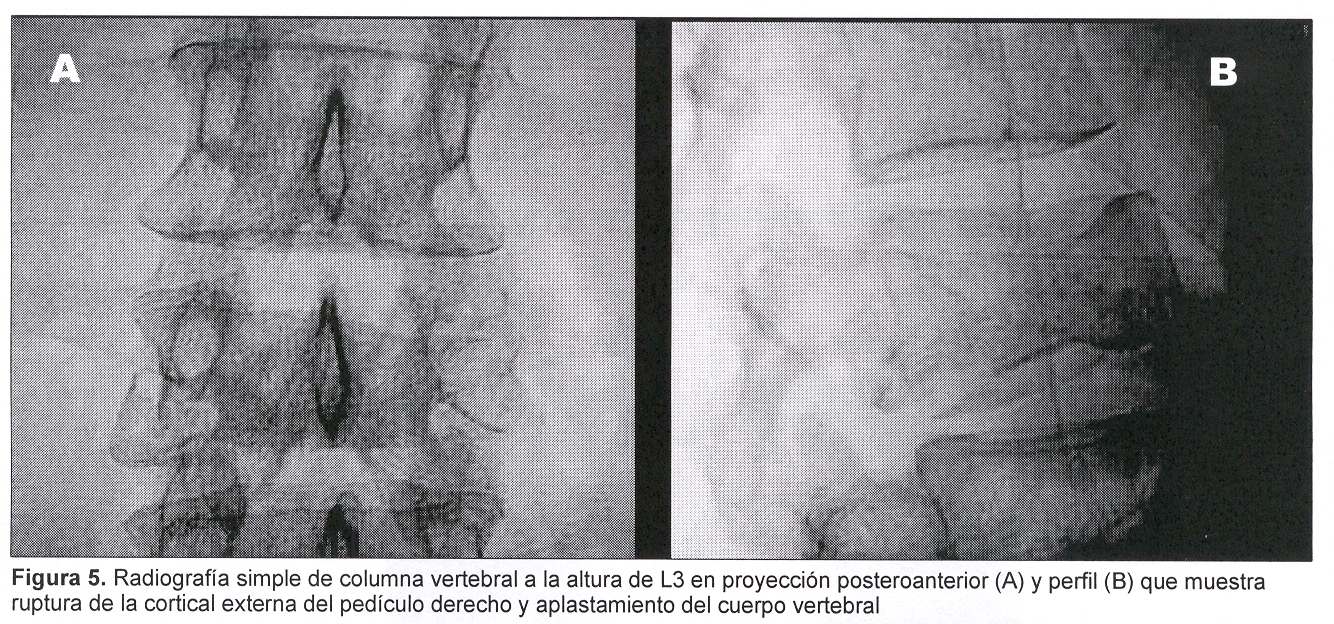

Sexo femenino, 43 años, con cuadro de 45 días de evolución dado por dolor raquídeo lumbar intenso, de comienzo súbito y evolución progresiva a pesar del tratamiento médico. Al igual que en el caso anterior el dolor era tan intenso que la obligaba a mantener reposo absoluto en cama. Al examen físico presentaba intenso dolor raquídeo a la palpación de L3, sin signología radicular ni deficitaria. Fue estudiada con radiografía simple (figura 5) y TC de columna lumbosacra que mostraban: aplastamiento del cuerpo vertebral de L3 a predominio de la plataforma inferior y falta de definición del pedículo derecho, múltiples imágenes líticas a nivel del cuerpo y del pedículo derecho con lisis parcial del muro posterior, abombamiento hacia el canal raquídeo (figura 6). Existían, además, otras imágenes líticas a nivel costal a la altura de la undécima costilla derecha. Las imágenes correspondían a sustitución ósea por metástasis. En esta paciente no existía noción de tumor primitivo por lo cual se planteó la realización de biopsia de la lesión concomitantemente con el tratamiento mediante vertebroplastia percutánea (figuras 7 y 8).